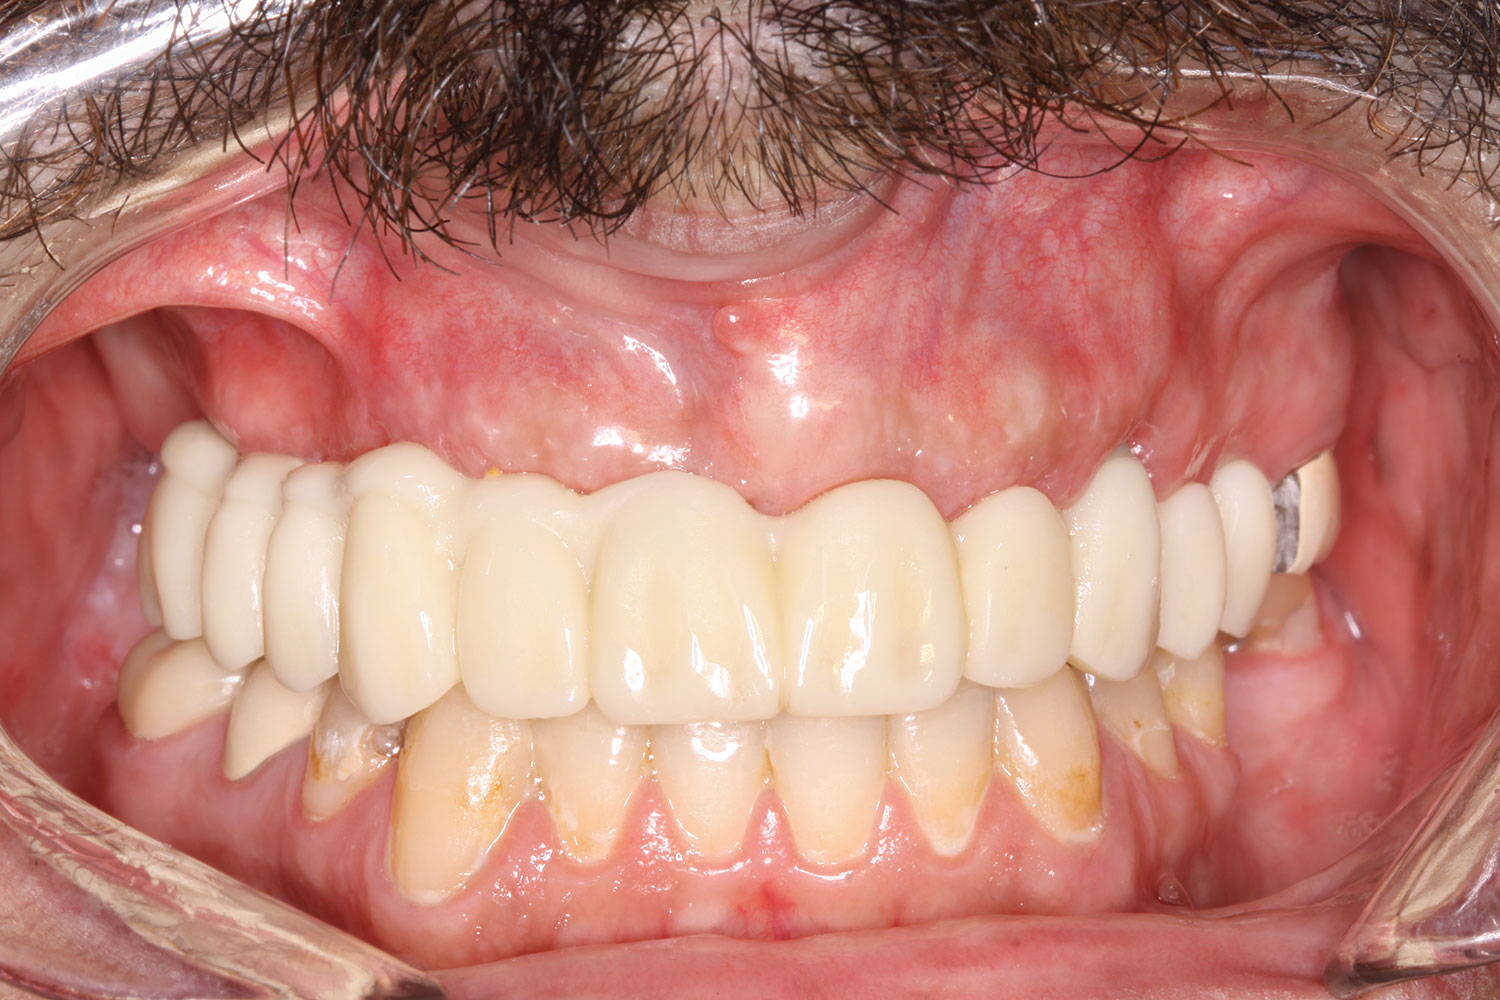

Fig 23. Case 3: Initial presentation for maxillary and mandibular immediate implant, immediate load provisional restorations. Full-face photograph.

Figure 23

Fig 25. Initial clinical presentation, intraoral view.

Figure 25

Case 3

A 67-year-old female patient presented with a highly compromised maxillary and mandibular dentition, including teeth Nos. 2 through 15, 17, 21 through 24, and 27 through 30. Soft tissues were of normal contour, and bone profiles were generally sustained and favorable. The patient was excited about the prospect of transforming both her maxillary and mandibular compromised esthetics and function in one visit. (Case 3 is depicted in Figure 23 through Figure 42.)